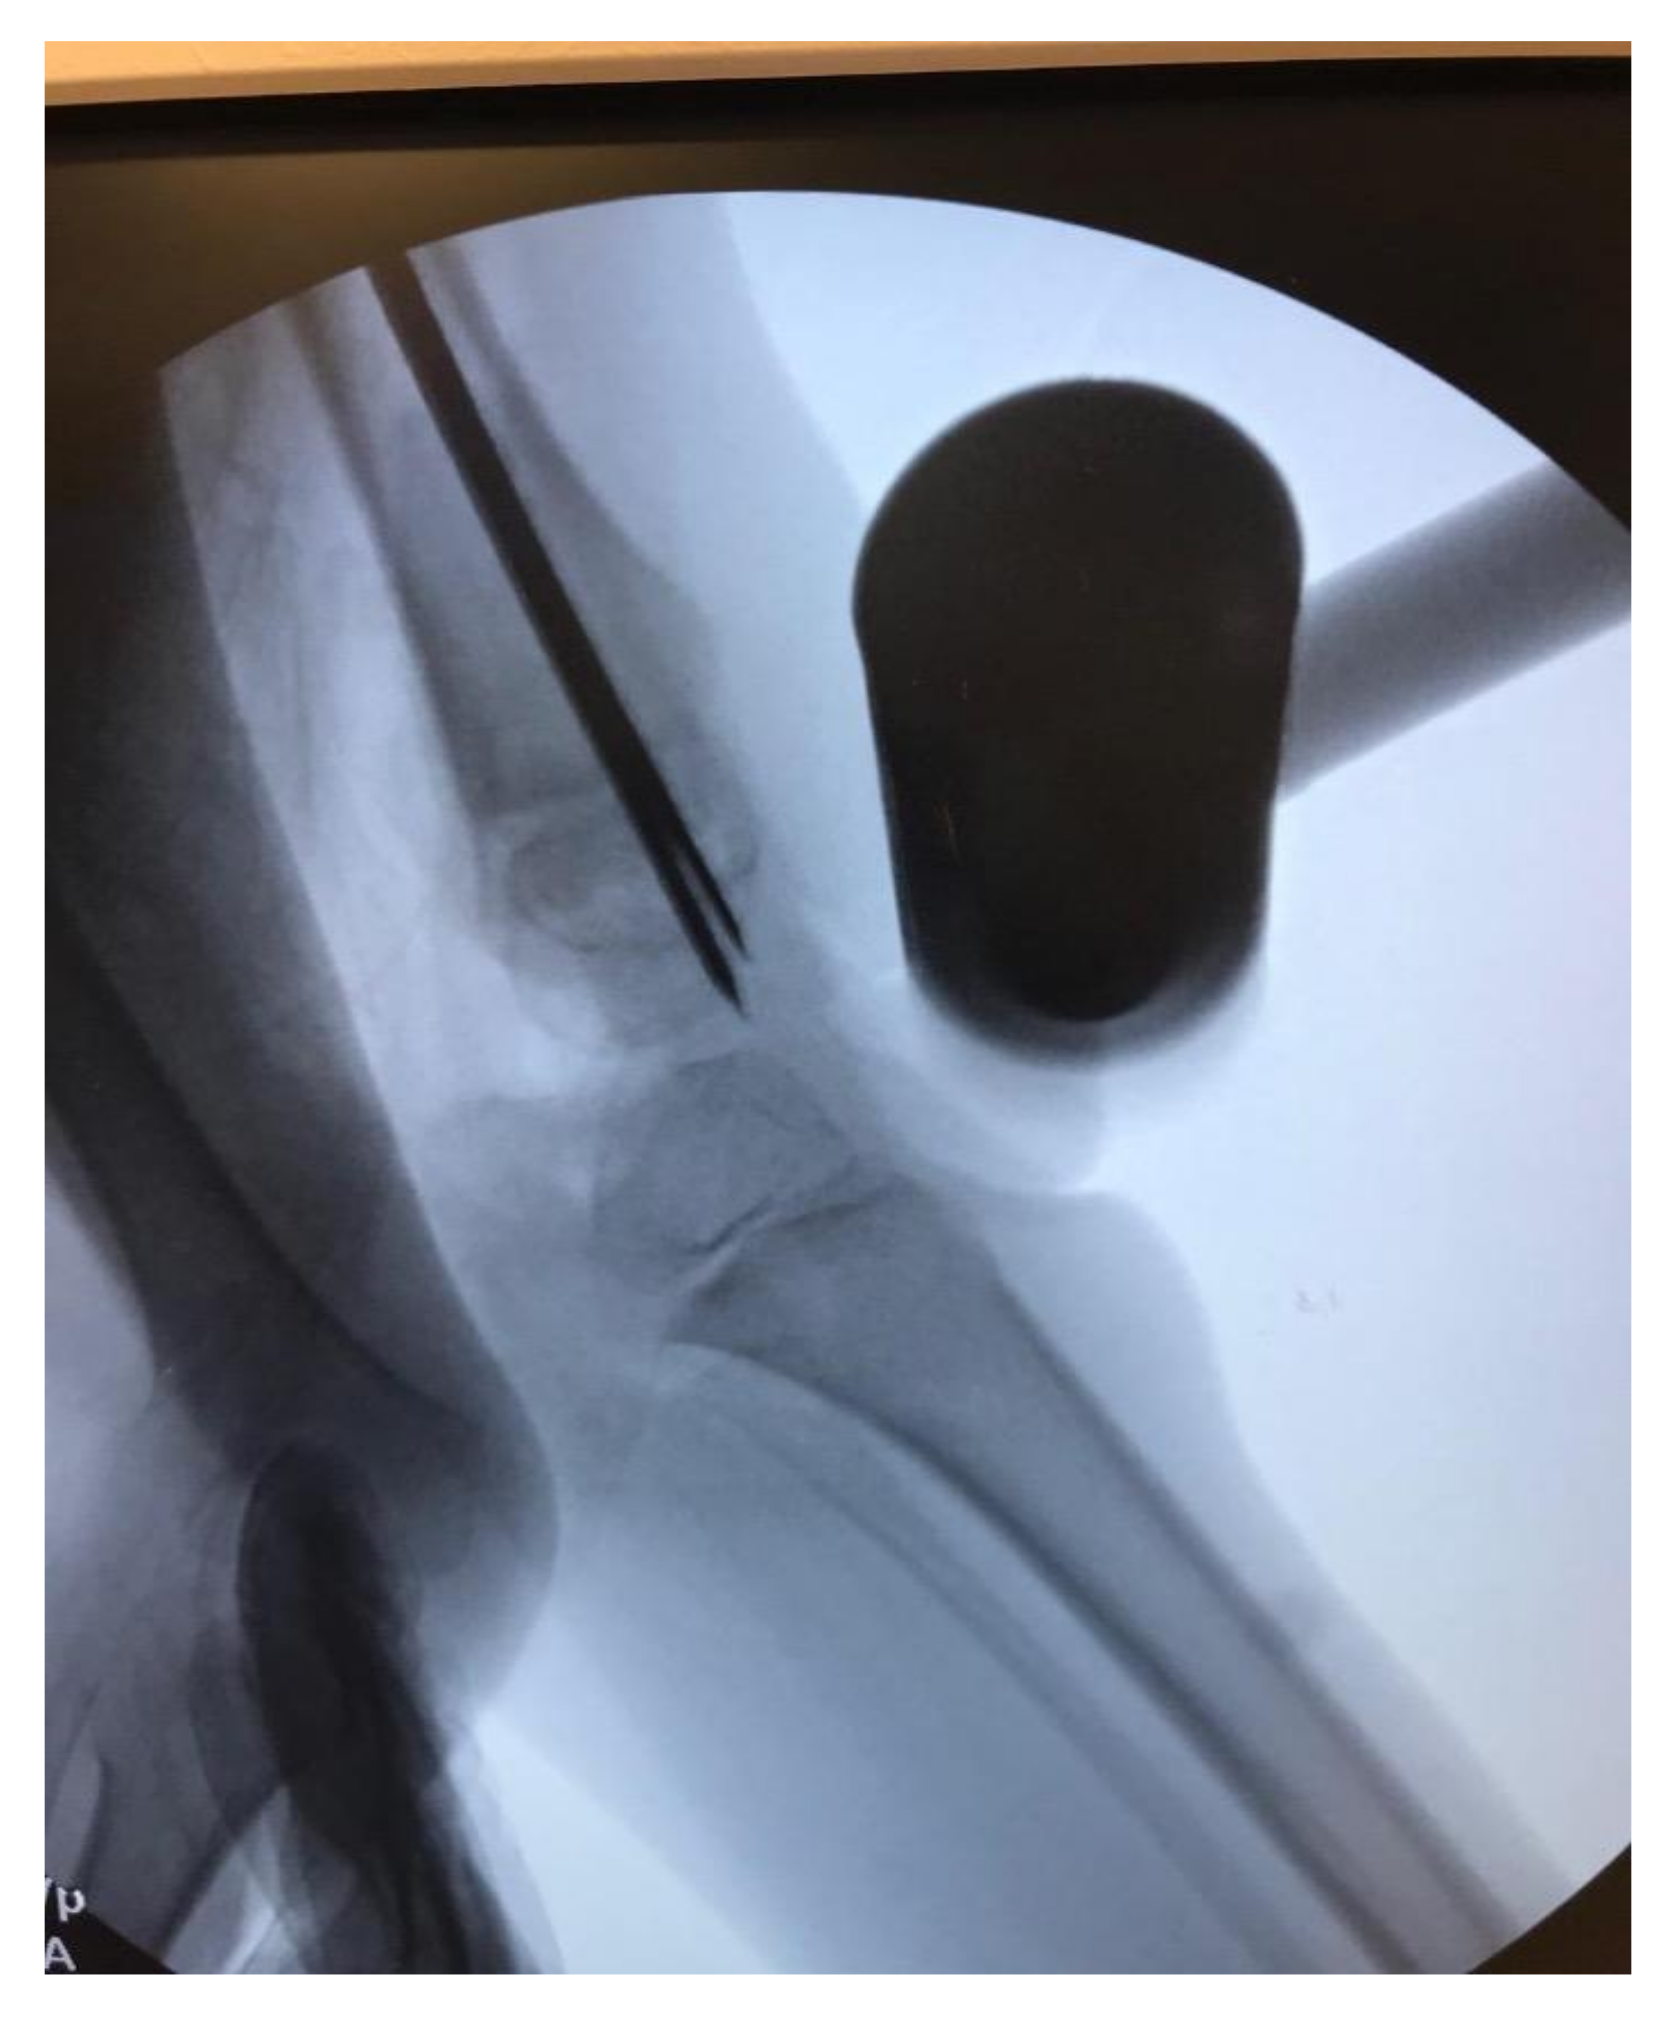

The incision is extended proximally to the subtrochanteric region and the remainder of the proximal femur is subperiosteally dissected. A wire for the appropriate, predetermined, diameter Slim™ rod (Pega Medical, QC, Canada) is inserted from the greater trochanter past the distal femoral physis. The canal is reamed to prepare for placement of the final rod. The length of the rod is determined by measuring the amount of wire in the canal (using another wire and ruler) and subtracting the presumed amount of shortening. For example, if the distance from the greater trochanter to just past the distal femoral physis measures 250 mm and you plan on shortening 50 mm then the rod length should be 200 mm. If the rod length is found to be incorrect, it can be exchanged after shortening osteoplasty. A rotational line is created on the femur with a sagittal saw and the first rod is placed just proximal to the osteotomy site. The osteotomy is performed, and the distal end is delivered out of the wound with a lion jaw. A second rod is placed into the distal femoral segment and into the distal epiphysis of the femur. A 1.8 mm wire is inserted down the canal parallel to the Slim ™ rod into the epiphysis. This is done to protect the physis (Figure 7). Prior to extending the knee the ends of the osteotomy are overlapped to allow shortening and loosening of the soft tissues, particularly the neurovascular bundle. (Figure 7) The knee is extended slowly indirectly releasing adhesions until full extension is obtained. Full extension of the knee is confirmed on a fluoroscopic cross-table lateral (Figure 8), the distal rod and wires are removed, and the overlap of the distal femoral segment to the proximal segment is marked on the distal femoral segment. The femur is shortened the marked amount and should allow for full extension of the knee. This is usually between 3–5 cm but there are times when more may be needed. The proximal rod is inserted into the distal shortened fragment and passed into the epiphysis distally and into the greater trochanter proximally. Rotation is controlled with either a six to eight hole 2.0–2.7 locking plate placed anteriorly or posteriorly to the intramedullary rod (Figure 9). It can be helpful to obtain a lateral fluoroscopic view of the femur to determine optimal plate position relative to the rod. Most often the screws are bicortical. Rotation is checked to be certain that what was once thought to be a rotational deformity may not be. The femoral bone removed from the shortening is ground and used as graft at the osteotomy site. The wound is closed over a 7 mm JP drain.

Figure 8. Fluoroscopic view of the knee in max extension after the proximal osteotomy; notice the wires and rod crossing the physis to protect it while the knee is extended.